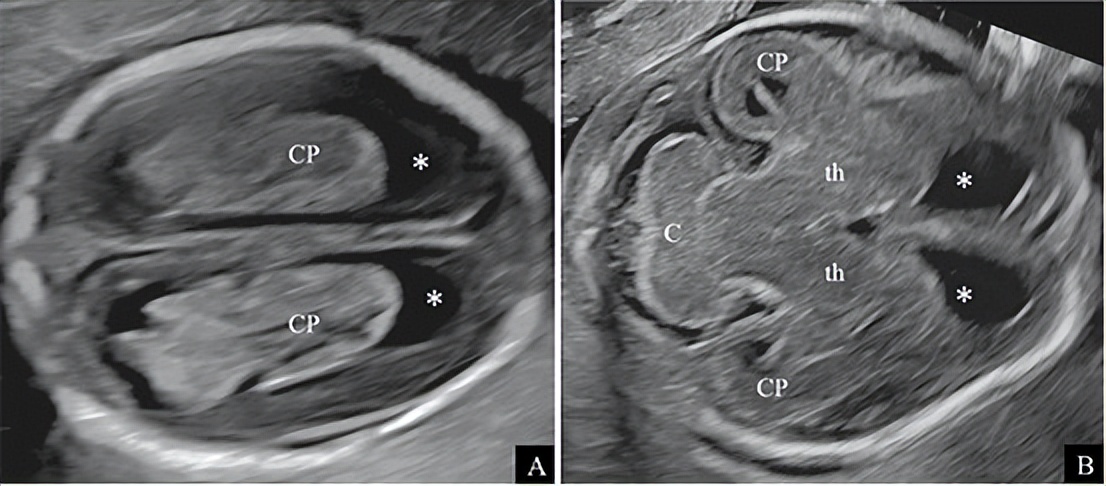

早孕后期和中孕早期的胎儿超声检查的应用越来越多,至今尚缺乏相关的临床应用指南。本指南建议,如果18周前进行超声筛查,应尽可能观察和记录侧脑室切面和小脑切面 (图6)(良好的实践证据),但应告知孕妇产前超声不仅存在技术的局限性,同时还具有时效性。

图6 正常16周胎儿 A:侧脑室切面:侧脑室较周围薄层脑实质显得宽大,额角(*所示)呈圆弧形,内充满脑脊液,脉络丛(CP)充满侧脑室的体部、室腔、枕角和颞角,边界可不规则;B:小脑切面,中孕早期小脑(C)呈哑铃状,上蚓部存在,呈等回声(妊娠后期则呈稍高回声)。可观察到的结构还有侧脑室前角(*所示)、丘脑(th)、部分侧脑室枕角和CP